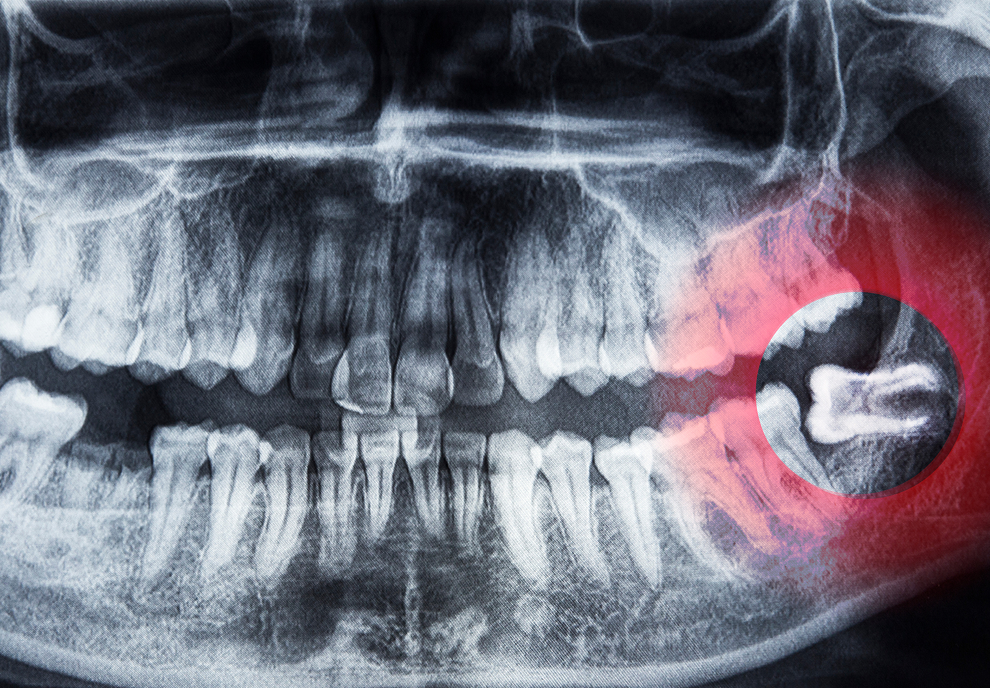

Having your wisdom teeth removed can be a scary experience, and the days following the surgery are often just as nerve-wracking. Fortunately, there are steps you can take to ensure that your recovery goes as smoothly and quickly as possible. In this blog post, we will discuss the essential post-operative care after wisdom teeth extraction, so you can recover quickly and get back to your normal routine.